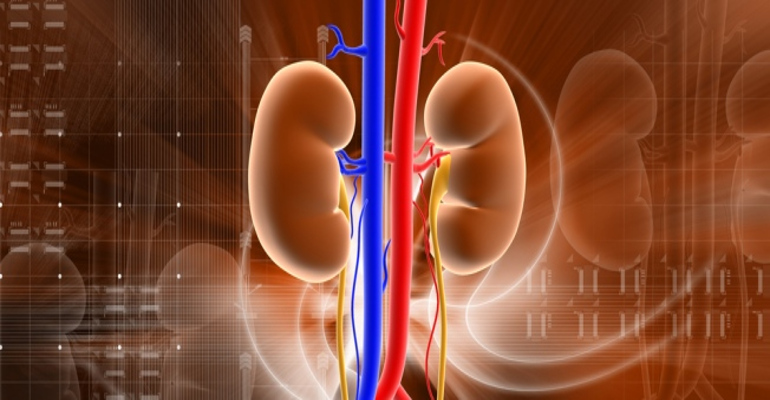

Περιτοναϊκή κάθαρση

Η περιτοναϊκή κάθαρση (ΠΚ) καθαρίζει το αίμα σας και απομακρύνει τα πλεονάζοντα υγρά χρησιμοποιώντας ένα από τα φυσιολογικά φίλτρα του οργανισμού σας, την περιτοναϊκή μεμβράνη.